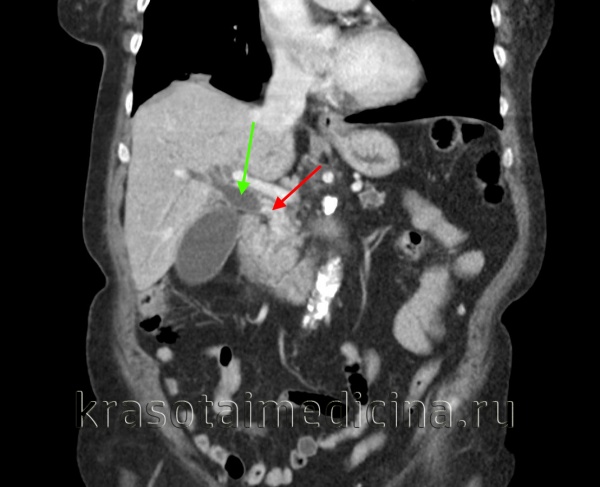

КТ ОБП. Внутрипротоковая холангиокарцинома (опухоль Клацкина) холедоха (красная стрелка). Расширенный холедох (зеленая стрелка). Расширенный главный панкреатический проток (желтая стрелка).

КТ ОБП (этот же пациент). Опухоль Клацкина холедоха (красная стрелка). Расширенный просвет холедоха до зоны обструкции (зеленая стрелка).